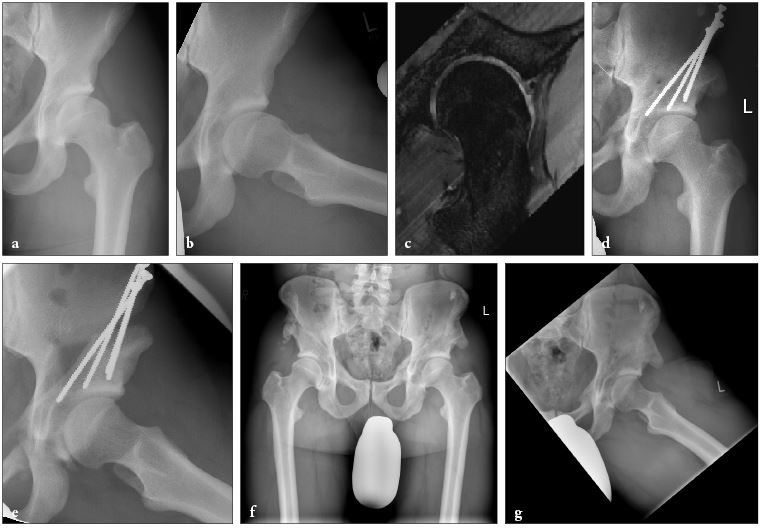

Crutches are recommended for about 8-10 weeks. Routine thromboprophylaxis is administered for the first 6 weeks. Fig. 8 shows the treatment result of a 22 year old male with a combination of AD and cam-FAI, where head-neck osteochondroplasty and microfracturing of acetabular cartilage defects have been performed.

Fig. 8: Combined AD and cam-FAI with pre-op radiographs (8a, b), pre-op radial MRI (8c),

postoperative radiographs after PAO with cam resection and microfracturing (8d, e) and final result after 12 years (8f, g)